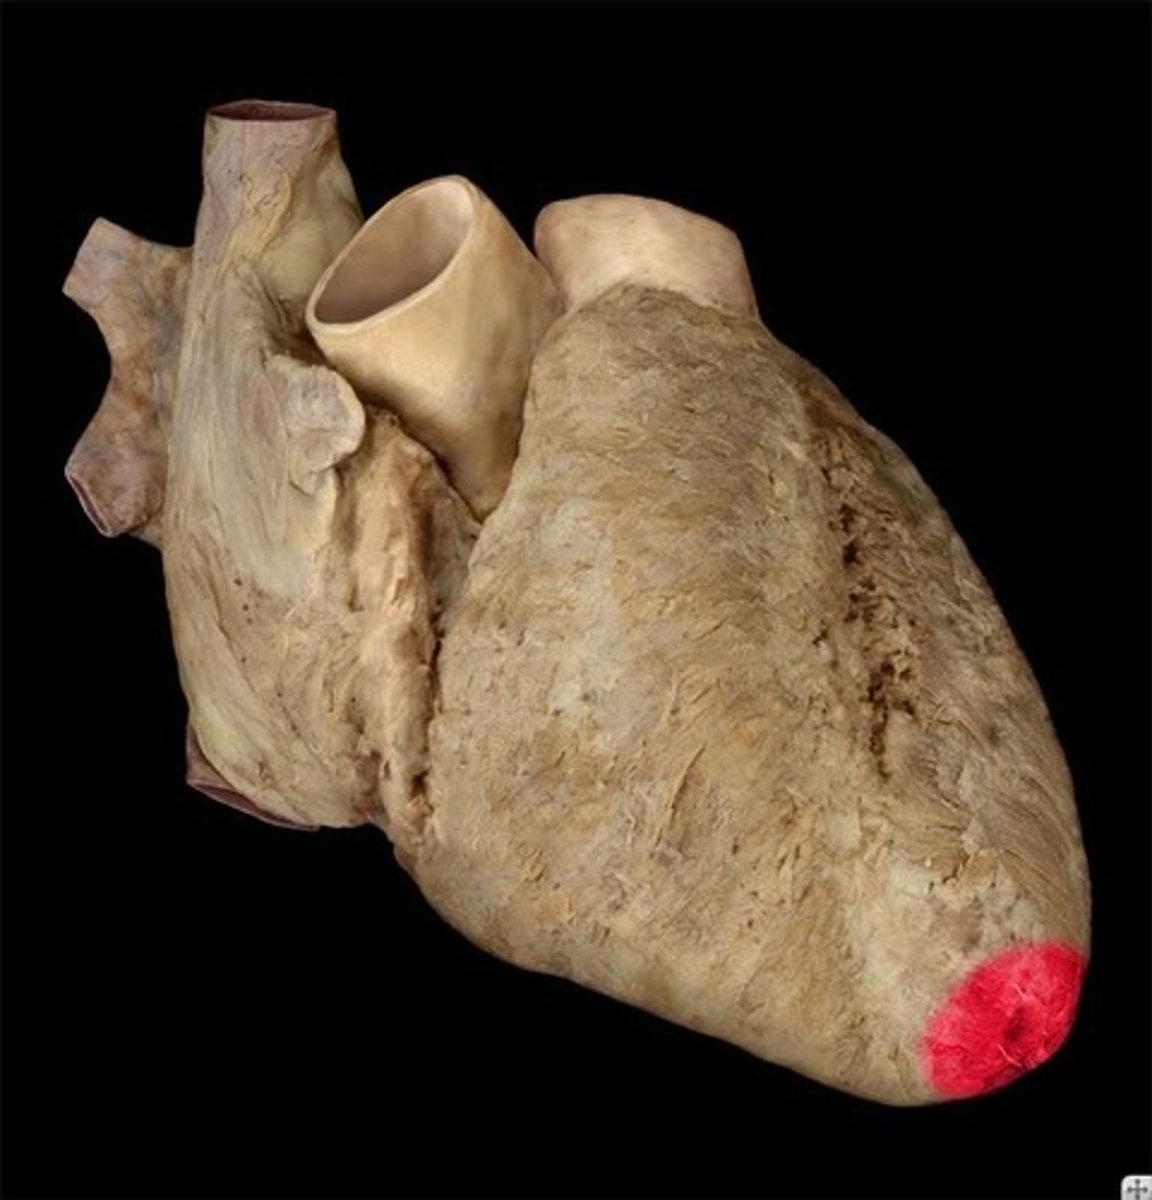

apex (of heart)